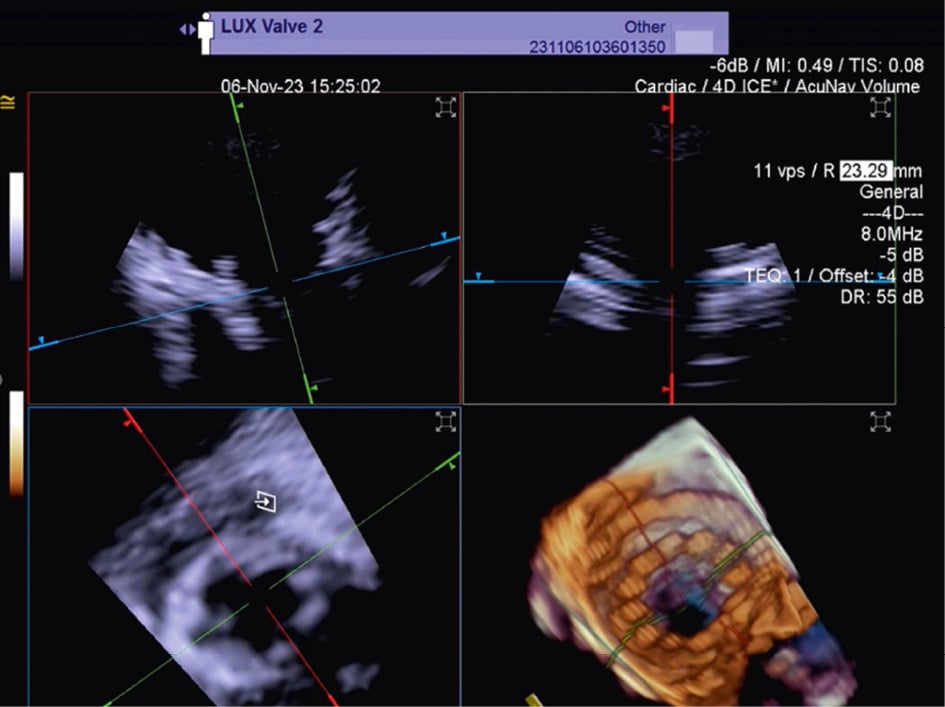

Although PFO/ASD procedures can be performed using a simple 2D ICE probe, in some more challenging anatomical settings (e.g., floppy interatrial septum [IAS], doubt about PFO/small ASD, particular PFO tunnel), 3D ICE can be of added value. When 3D ICE is used for PFO or ASD procedures, positioning within the right atrium is sufficient. With 3D ICE, the septal defect can be visualised in a 3D volume and typically only a catheter position is needed. When starting the procedure, the operator should screen patients for additional septal defects that may have been missed on the preprocedural imaging and determine whether there is a floppy interatrial septum (for PFO) and a sufficient superior and inferior rim (for ASD). Three-dimensional ICE allows us to determine the size of the septal defect (especially for an ASD closure), guide occluder deployment, verify placement post-deployment, and screen for residual shunts1 (Figure 12, Figure 13, Moving image 18-Moving image 19-Moving image 20-Moving image 21-Moving image 22).

Figure 12. Three-dimensional ICE-guided patent foramen ovale closure. A) 2D imaging allowing assessment of needle tenting in the middle of the fossa ovalis. B) Biplane imaging allowing assessment of the catheter after crossing the septum in the superior-inferior and anterior-posterior positions simultaneously. C) 3D multiplanar reconstruction (MPR) allowing assessment of the catheter after crossing the septum. D) 2D imaging showing the deployment of the right disc of the device. E) 3D MPR allowing simultaneous assessment in the lateral, axial, and azimuthal planes of the right disc of the device. F) 3D reconstruction of the device. 2D: two-dimensional; 3D: three-dimensional; ICE: intracardiac echocardiography

Figure 13. Three-dimensional multiplanar reconstruction views of the device in the interatrial septum.

Moving image 18. Biplane imaging allows assessment of the catheter after crossing the septum in superior-inferior and anterior-posterior positions simultaneously.

Moving image 19. 3D RT MPR allowing assessment of the catheter after crossing the septum.

Moving image 20. 3D MPR allowing the simultaneous assessment of the right disc of the device in the lateral, axial, and azimuthal planes.

Moving image 21. 3D MPR views of the device in the interatrial septum.

Moving image 22. Colour biplane imaging showing the device in the interatrial septum with no residual shunts.